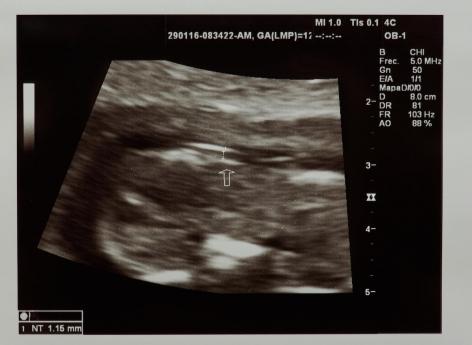

Tout commence en novembre 2016. À ce moment-là, Lucie, 27 ans, tombe enceinte. C’est en tout cas ce qu’elle croit puisqu’elle présente tous les signes d’une grossesse. “Puis un jour, je me mets à avoir très mal aux reins, assez pour que mon mari me conduise aux urgences, se souvient-elle. D'échographie en échographie, nous voilà avec un gynécologue et alors que je demande à mon mari s'il aperçoit le bébé sur le moniteur, le couperet tombe.” Le médecin lui annonce que le moniteur n’affiche pas de bébé mais une tumeur trophoblastique gestationnelle. Ce type de tumeur bénigne, également appelée grossesse molaire, se caractérise par la formation d’une masse de kystes appelée môle hydatiforme à la place d’un embryon normal.